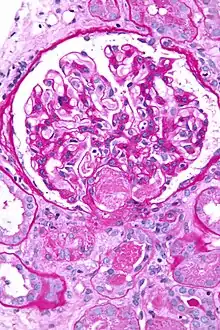

![]() صورة مجهرية showing an acute thrombotic microangiopathy, the علم الأنسجة correlate of DIC, in a خزعة كلوية. A خثرة is present in the نقير of the كبيبة (توضيح) (center of image). PAS stain. صورة مجهرية showing an acute thrombotic microangiopathy, the علم الأنسجة correlate of DIC, in a خزعة كلوية. A خثرة is present in the نقير of the كبيبة (توضيح) (center of image). PAS stain. | |